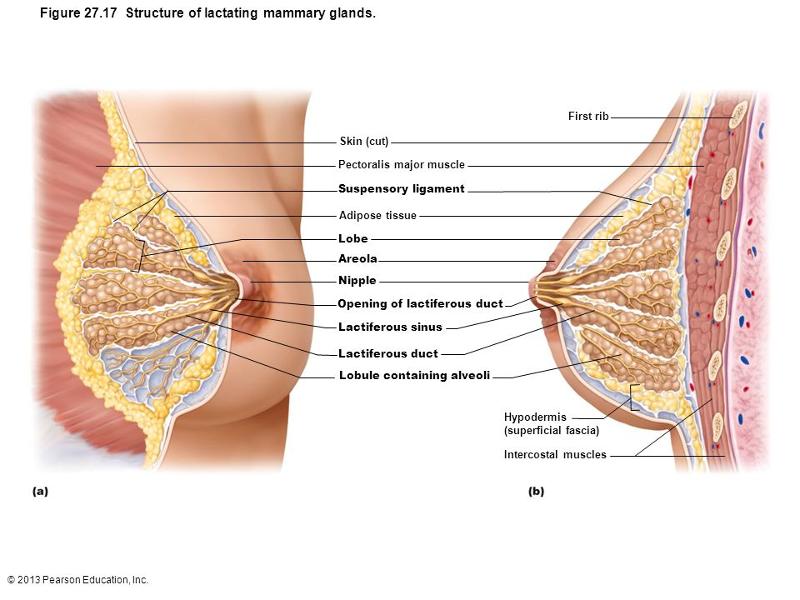

mammary gland

interlobar connective tissue that attaches the breast tissue to the underlying muscle fascia and overlying dermis is called

suspensory ligament

coumpound alveolar glands of the breast produce milk which is carried through the duct to the nipple. the dilated portion of the duct just deep to areola is called

lactiferous sinus